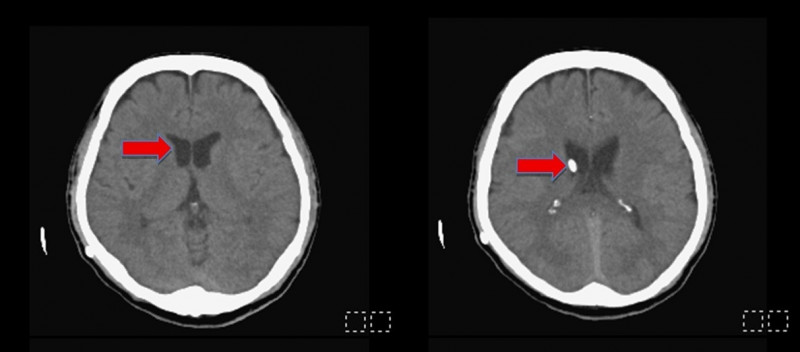

〔記者許麗娟/高雄報導〕48歲油漆工工作不慎撞到頭,導致頭部外傷、顱內出血,就醫後接受保守治療未開刀,但某日突然出現意識不清、嗜睡送到醫院急診,腦部電腦斷層檢查發現腦室腫大為水腦症,經緊急手術引流腦脊髓液,術後已恢復意識、改善行動力,亦已重返工作崗位。

該名油漆工頭部受傷後未手術,採保守治療,家屬因照顧問題送至安養機構入住,因意識不清、嗜睡送來急診時,因腦室明顯腫大,緊急進行「腦室腹腔分流手術」,於腦室置放引流裝置並連接至腹膜腔,將蓄積多餘的腦脊髓液排出,患者病症大幅改善。

陳志豪強調,早期辨識與介入治療是改善預後的關鍵,臨床可透過電腦斷層(CT)或磁振造影(MRI)影像學判斷及病程追蹤來評估是否需進行分流手術。此個案是手術後才恢復清楚意識及記憶,術後半年追蹤,原先腫大的腦室已恢復正常大小,並已恢復如常的生活。